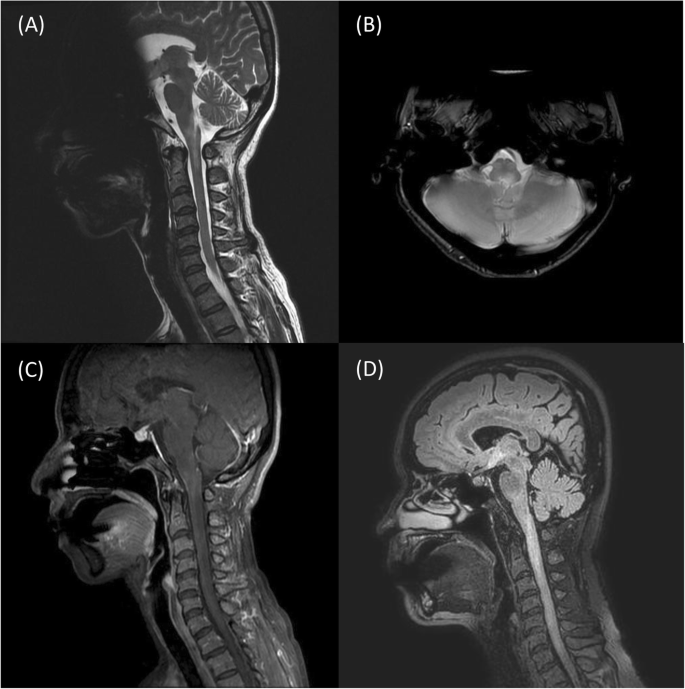

Figure 1 shows a representative case of NMOSD. A 47-year-old female had subacute onset of a spinning sensation, unsteady gait and recurrent nausea and vomiting for one week. Sagittal-view brain MRI showed a hyperintense lesion in the area postrema that extended to the first vertebral body (Figs. 1 a & b). Gd-enhanced T1-weighted images showed contrast enhancement in the corresponding regions (Fig. 1 c). Her level of anti-AQP4 antibody was 4.46 units/mL. Her EDSS score at three months was 2. Two years after initial presentation, she had a recurrent attack presenting as bilateral upper-limb numbness for two weeks along with right visual impairment. Brain MRI showed an extended lesion from the area postrema to the secondary vertebral body on the Gd-enhanced T1-weighted images (Fig. 1 d). The patient’s EDSS score at three months was 3.5.

Brain MRI showed a representative case of a patient with NMOSD. a. A T2-weighted hyperintensity lesion at the area postrema that extended to the first cervical vertebral body level on the MRI sagittal view. b. The brain MRI axial view showed a hyperintense lesion at the area postrema that was more severe on the left side of the medulla. c. A [Gd]-enhanced lesion from the medulla to the first cervical vertebral body level on the sagittal-view T1-weighted contrast image. d. A hyperintense lesion from the area postrema extended to the secondary vertebral body level on the sagittal-view FLAIR image was noted 2 years after the first attack